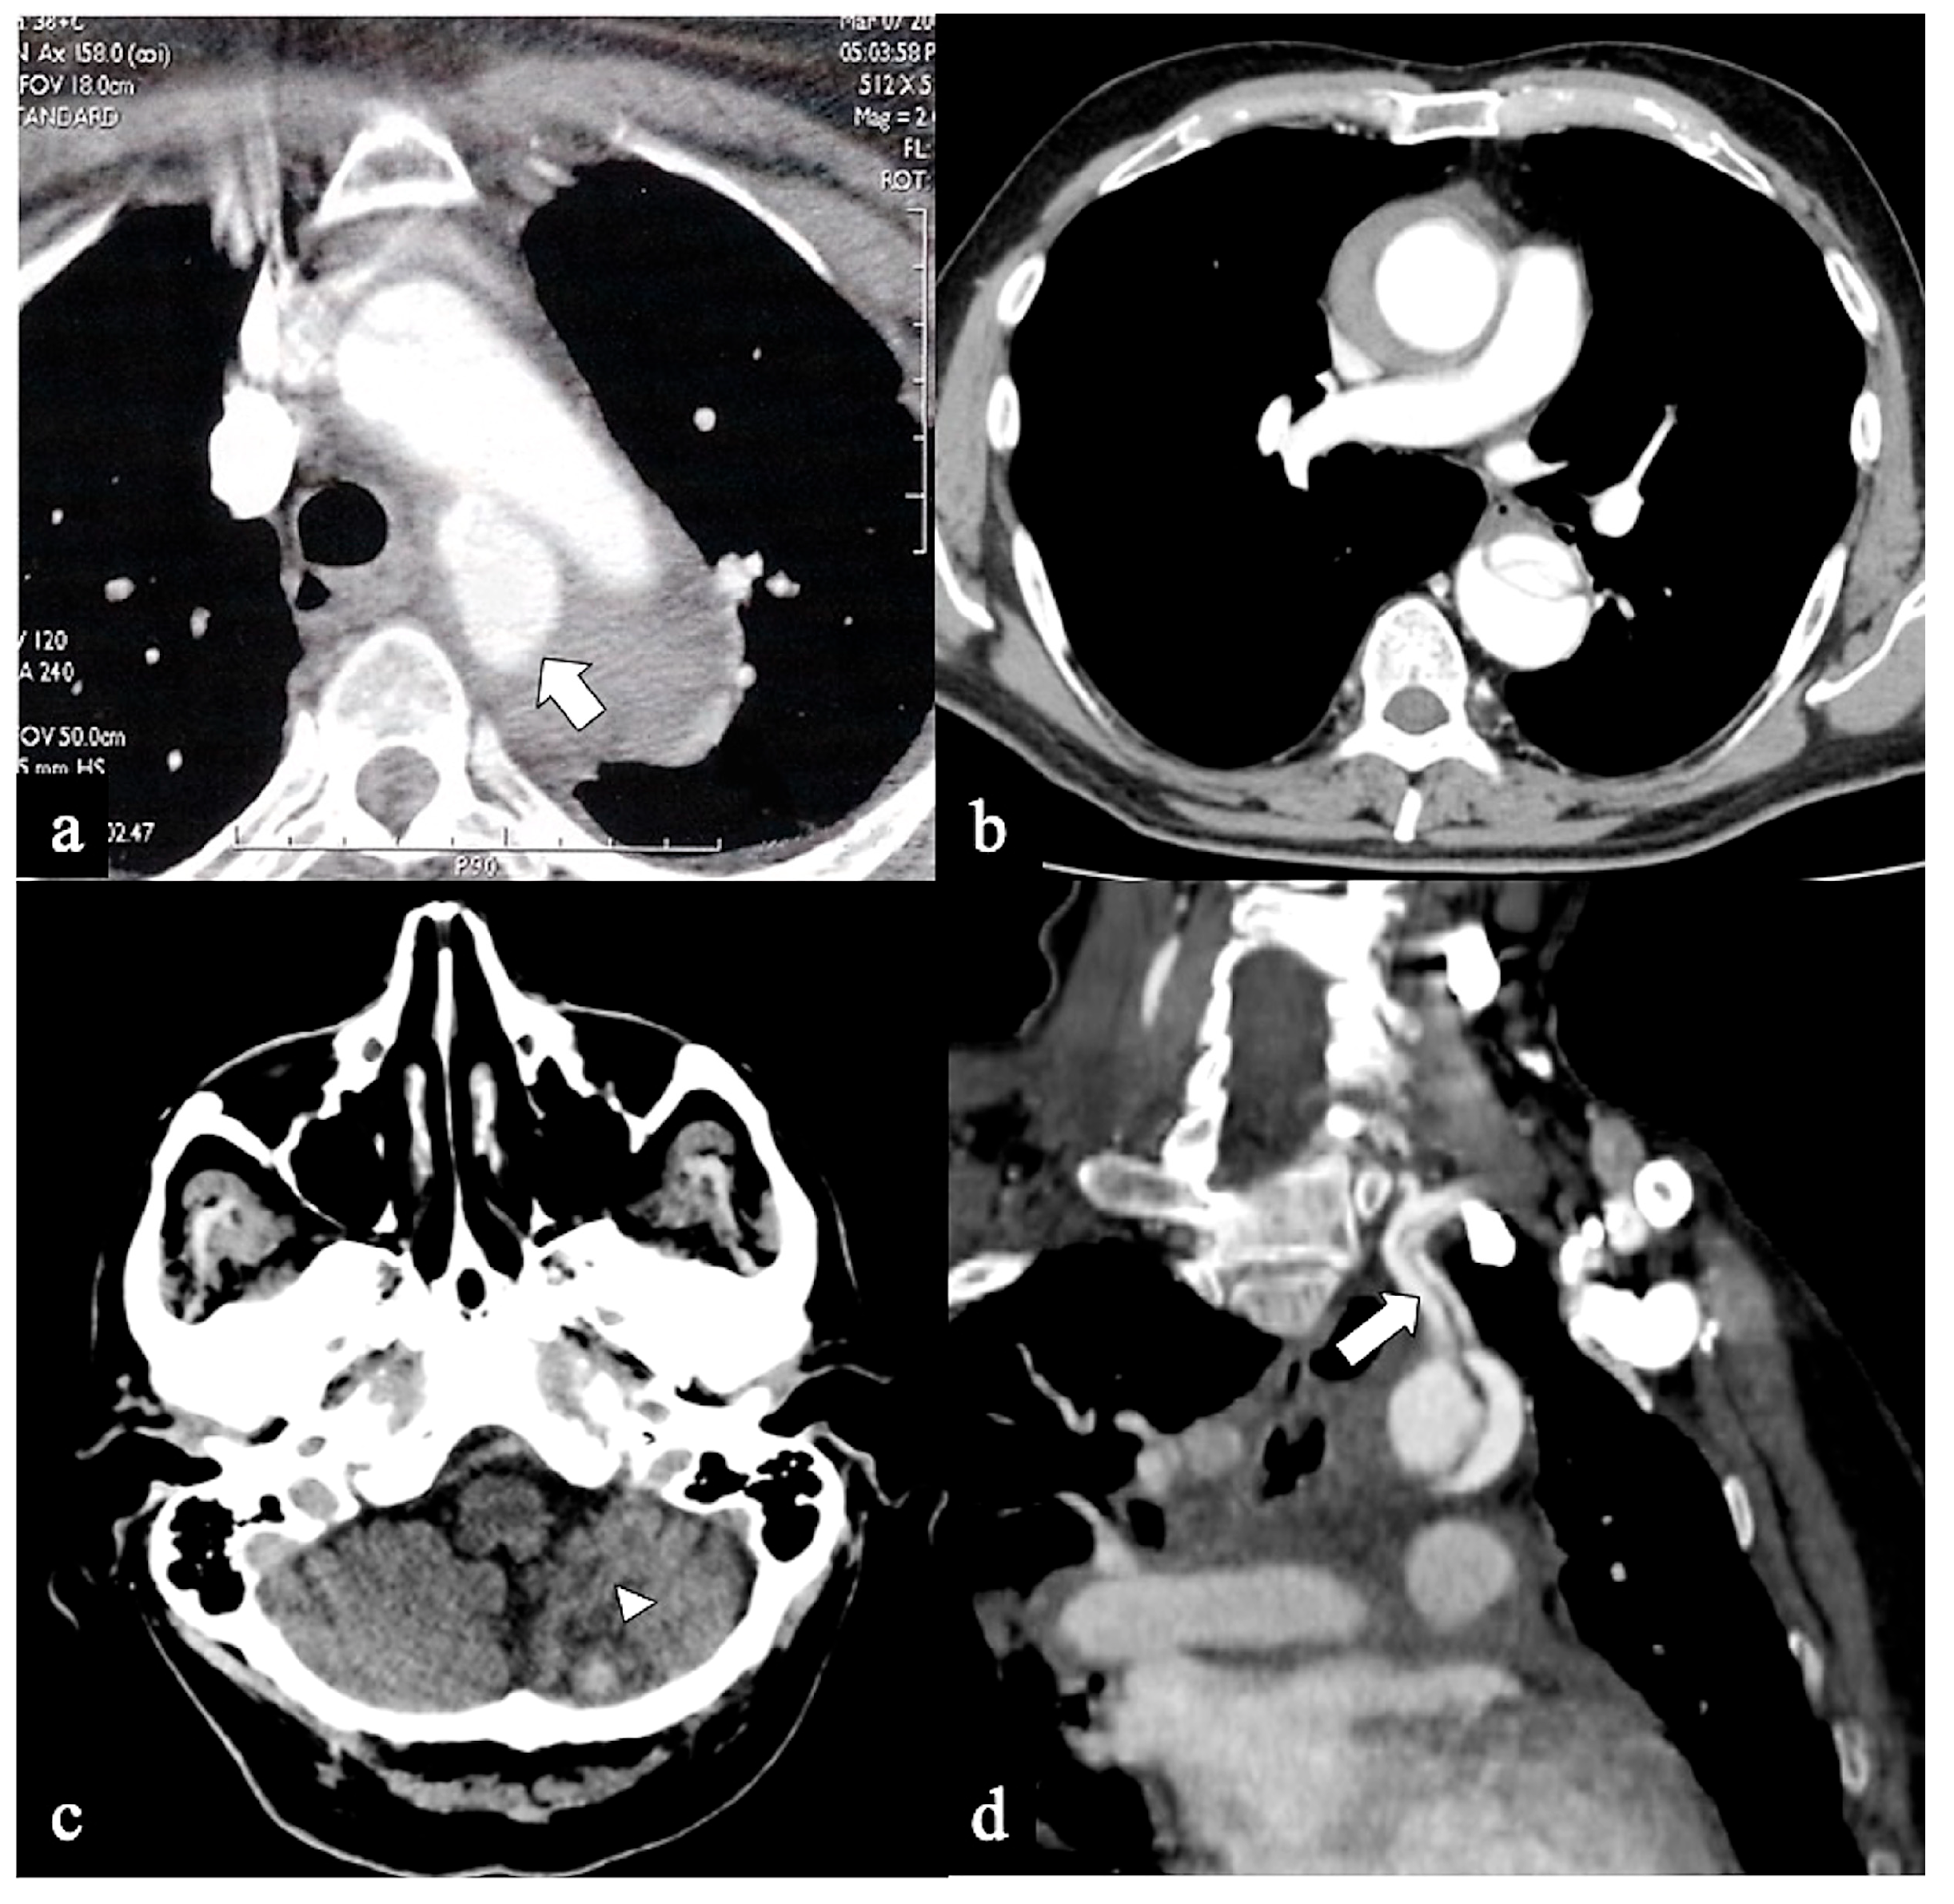

- Configuration 1 (or DTA entry): Among the cohort, 25 out of 36 patients (69.5%) presented with a type B AD or descending-entry type, with the primary entry tear distal to the left subclavian artery (zone 3). The extension of the flap occurred antegradely into the descending aorta, with or without the involvement of the abdominal aorta, and retrogradely into the aorta until the brachiocephalic trunk (BCT) (Figure 3). We describe this configuration as non-A non-B dissection with a retrograde pathway of dissection, as the entry site of the flap is in the descending aorta with retrograde arch involvement. According to Stanford classification, this configuration was present in 14% of type B AD patients. Previous studies have documented DTA entry type to be present between 10% and 25% of patients with acute type B dissection, sometimes as an intramural hematoma [33,34,35]. Patients presenting with DTA entry non-A non-B dissection demonstrated a prevalent origin of BCT and LCCA in 20% and an arch origin of the left vertebral artery in 4%. Among these cases, the distal extent of dissections was observed in various locations: the thoracic aorta in 9 patients, the abdominal aorta in 7 patients, and the pelvic circulation in 9 patients. Involvement of specific arteries was noted, including the left subclavian (n = 5), left common carotid (n = 1), or innominate (n = 1) arteries. Six of these DTA entry patients, who were initially managed with medical therapy, necessitated hybrid or surgical aortic repair within 10 days after the onset of dissection due to persistent pain (3/5), new organ malperfusion (2/5), or rapid aortic growth (1/5). Forty percent of these patients underwent treatment with optimal medical therapy and close imaging surveillance, while 60% received hybrid or open surgical therapy.

- In Configuration 2, the primary ET is situated within the aortic arch, and the dissection flap is confined solely to the arch (Arch alone). the primary ET is located in the aortic arch and the dissection flap is limited to the arch (Arch alone). This very uncommon configuration occurred in 4 (11%) patients (Figure 4) and is a very rare clinical entity. Configuration 2 is similar to the “group B” definition provided half of a century earlier by Dubost and colleagues [36], reported by Pasic in 1999 [37], and again proposed by Urbanski in 2016 [26]. An amount of 2/4 of these Arch alone patients received continued medical management with close imaging surveillance, and one- and two-year follow-up CTA examinations showed no dissection progression; 2/4 patients underwent hybrid or open surgical repair, one due to persisting pain, and the other one for cerebral malperfusion on follow-up CT.

- In Configuration 3 (Arch entry), the primary ET is situated within the aortic arch, and the flap extends into the DTA without affecting the ascending aorta [38]. This Configuration 3 occurred in 7 (19%) patients (Figure 5a,b). This AD configuration was already described as proximal type B dissection according to 2010 AHA guidelines [7] and recently reported as arch B group AD from IRAD [38] and as non-A non-B acute AD with entry tear in the aortic arch [39,40]. In this configuration, the ET was often located in the greater curvature of the arch (4/6), while in one case (1/7) its location was not clearly identified. In total, 4/7 of these patients underwent hybrid and 2/7 surgical therapy.